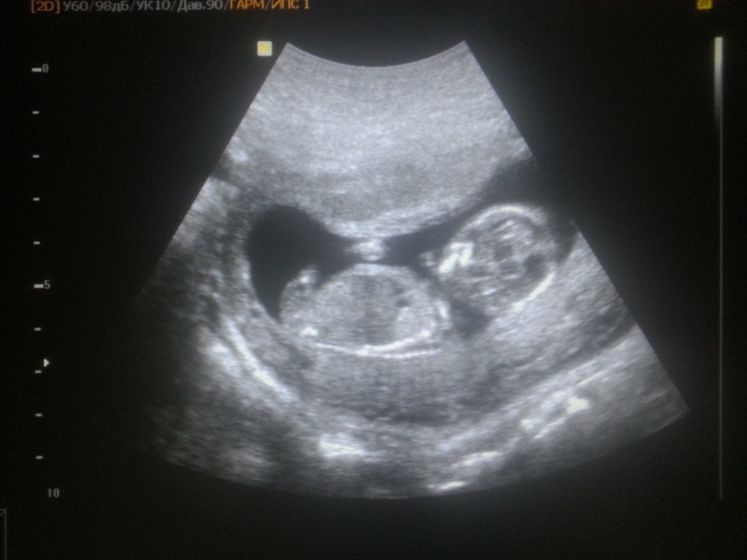

Уррааа)) это было очень трудно дождаться первой встречи)

Все у нас хорошо)

Какой крошка.Я 19 го иду на УЗИ)

Тьфу тьфу тьфу, просто я вчера на УЗИ была, и сказали что есть угроза так как деформированное плодное яйцо, в норме оно должно быть круглое, а у меня вытянутое. И сейчас вот у вас посмотрела тоже вытянутое, по этому спросила)

Это еще какой ракурс взять наверно. Потому что мне в реальном времени когда малышарика показывали, у него еще там ножки вытянуты длинные. В общем удобно устроился) я себе даже не могу представить как бы он в шаре сидел))